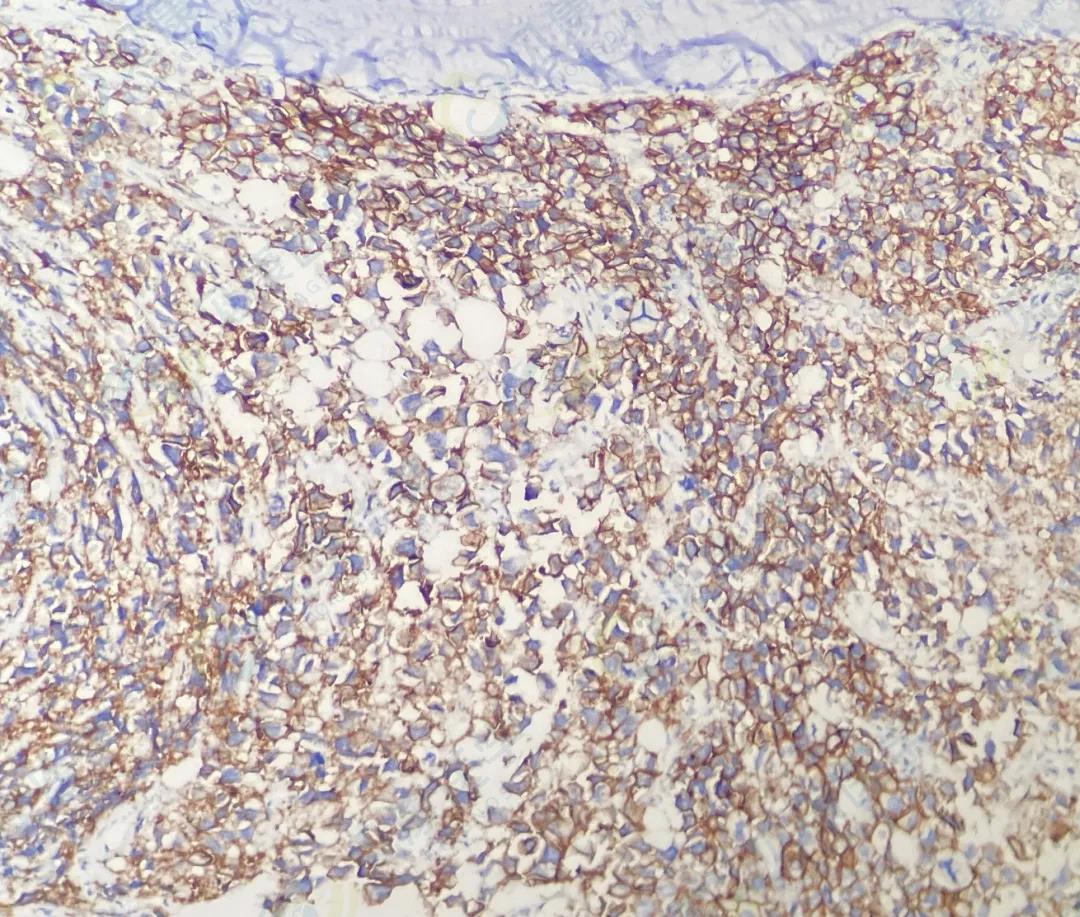

CD138

CD38